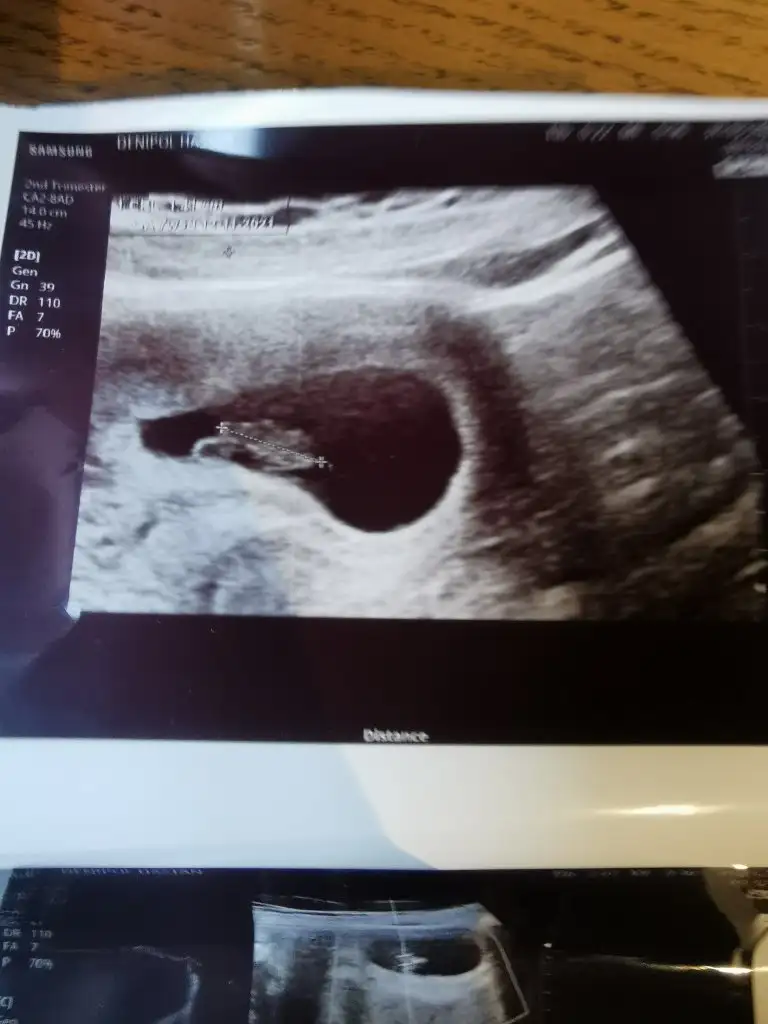

Ramzi teorisine göre ( bilimsel bir araştırma sonucuymuş ve %85 doğruluğu varmış). İlk 6-8 haftalık ultrason görüntüsüne göre bebeğin kesenin içersinde soldan ya da sağdan girişine göre cinsiyet tahmini yapılıyor. Bilimsel olunca tecrübeli annelerimiz yada anne adaylarımızdan yardım istiyoruz. Doğruluğu var mı öğrenmek adına :) Bizleri aydınlatırsanız çok seviniriz. bu teorieye göre;

Vajinal muayeneyle bakıldıysa eğer;

Sağdan girmiş gözüküyosa aslında solmuş ve ERKEK,

Soldan girmiş gözüküyosa aslında sağmış ve KIZ ,

Karından bakıldıysa eğer,

Soldan girmiş gözüküyosa gerçektede solmuş ve ERKEK,

Sağdan girmiş gözüküyosa gerçekte de sağmış ve KIZ,

Benimkinede bakarmisiniz 7 haftalikti burda karindan ultrasyonPlesanta solda bebekte solda karindan ultrasyonsa erkek